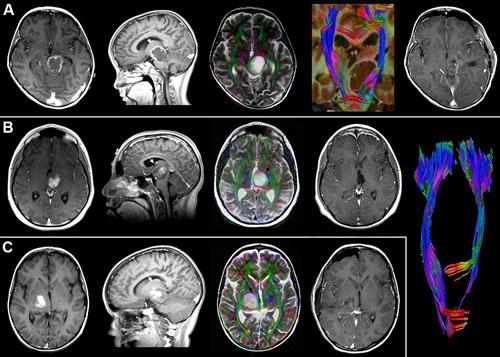

December 4, 2009 - Operative plans for removing juvenile pilocytic astrocytoma, or JPA, tumors in the thalamus of the brain can be augmented with diffusion tensor imaging, or DTI, according to a new study published in last week's issue of the Journal of Neurosurgery: Pediatrics.

DTI, a variation of MRI, can help identify white matter, or nerve fiber bundles, using specific radio-frequency and magnetic field pulses to track the movement of water molecules of the brain. In most brain tissue, water molecules diffuse in all different directions. But they tend to diffuse along the length of axons, whose coating of white, fatty myelin holds them in. Scientists can create pictures of axons by analyzing the direction of water diffusion.

The sensitivity of DTI imaging allows for the visualization of nerve fiber bundles in the brain. This information can maximize the potential of completely removing the tumor, while avoiding damage to the fiber bundles that are directly related to motor functions of the patient.

“This study of six children with thalamic JPA showed that using advanced MRI technology can help identify distorted nerve fiber bundles around brain tumors,” said Jeffrey H. Wisoff, M.D., director of the Division of Pediatric Neurosurgery at NYU Langone Medical Center. “This allows an otherwise inoperable tumor to be completely removed which can hopefully lead to a cure.”